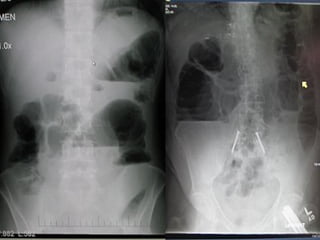

Investigations: • Radiographs areessential to confirm the diagnosis and accurate the site of the obstruction. • The radiological diagnosis is based on a supine(erect) abdominal radiograph. • If conditions of the patient are poor a lateral decubitus position view may be taken. • Usually can determine whether small bowel, colon or both are distended. • Radiographs show multiple gas-fluids levels, with distended bowell resembling an inverted U.

• 19.

• Obstruction ofthe small bowel outlines the valvulae conniventes, which occupy the entire transverse diameter of the bowel image. • Small bowel pattern occupies the more central portions of the abdomen. • Large bowel obstruction shows haustral markings, that occupies only a portion of the transverse diameter of the bowel, unlike valvulae conniventes, are spaced irregularly and the indentations are not placed opposite one another. • Large bowel pattern occupies the periphery or pelvis portion of the abdomen. • A distended caecum is shown by a rounded gas shadow in the right iliac fossa.

• 22.

• Large bowelobstruction with competent ileocecal valve show colon distention and little small bowel gas. • Large bowel obstruction with incompetent ileocecal valve shows small and large bowell distention and fluids levels. • Barium enema performed carefully may give the diagnosis of colonic obstruction. • At times is difficult to distinguish paralytic ileus from mechanical obstruction radiographically. • In paralytic ileus gaseous distention occurs uniformly in stomach, small bowel and colon. • In paralytic ileus gas-fluid levels may be seen. • Others investigations include: Serum electrolytes, Full hemogram, coagulation profile, renal function test, etc.